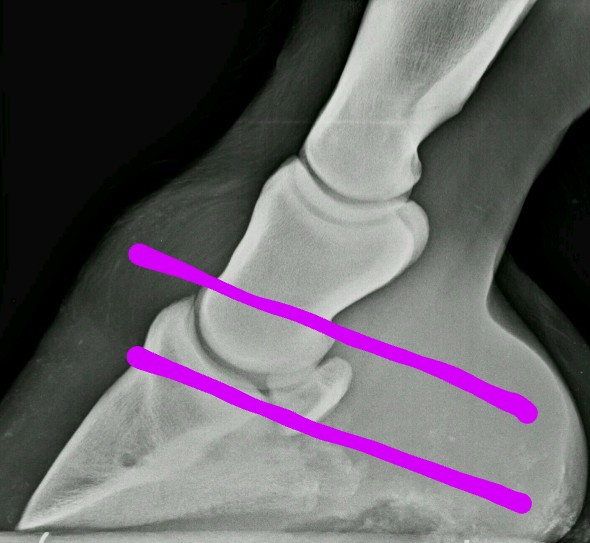

På bilden nedan ser vi hoven i genomskärning mitt genom hoven från sida till sida. Till höger syns strålen sticka ner, till vänster ser man sulan som sitter fast i hovväggen längst till vänster. Man ser oxå skon som hoven står på.

När väggen ensamt bär all vikt trycks den uppåt av markens tryck underifrån.

Det kan ske eftersom sulan är elastisk och ger efter. Hovväggen tar med sig kanten på sulan som fäster i den.

Som ni ser så är sulan inte längre slät och skålad, utan den får en böj uppåt där den möter hovväggen. På bilden syns det tydligast på “gropen” som bildas, men som inte syns utifrån, för den är på insidan av sulan.

Man kan ofta även se det på sulans utsida mot marken, skålformen försvinner även där och det blir som en utbuktning i sulans utkant mot väggen.